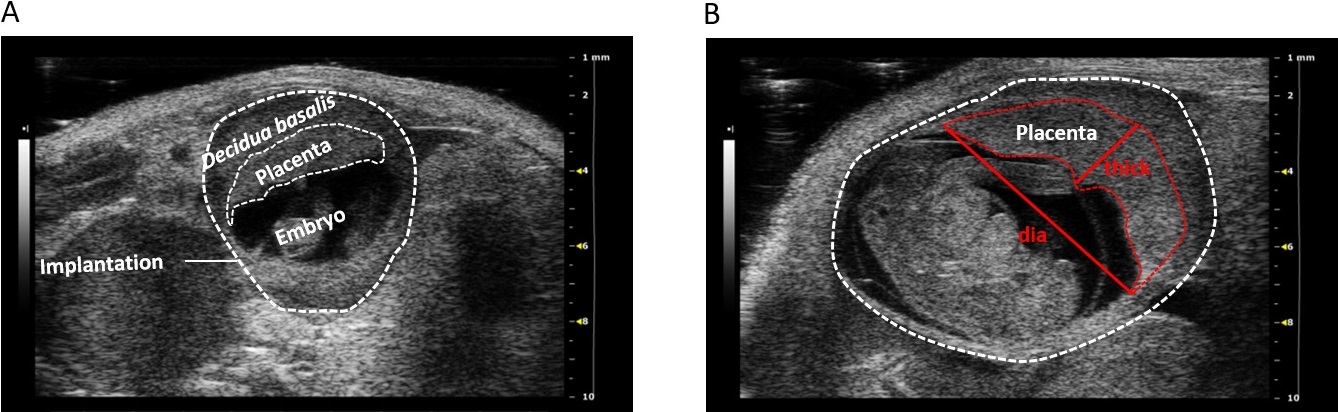

Einsatzgebiete im Rahmen der Forschung sind die Kardiologie, Entwicklungsbiologie, molekulares Imaging, Onkologie, Neurobiologie, Urogenital- und Gefäßbiologie sowie Schwangerschaftsforschung[1]. Daneben kann der Einfluss von Umweltchemikalien in vivo eindrucksvoll untersucht werden. Durch den Einsatz von Ultraschall während der Schwangerschaft können fötale Beeinträchtigungen früh erkannt werden. Das VEVO 2100 Imaging System ermöglicht es uns, Föten und Plazenten in trächtigen Mäusen in vivo während des gesamten Schwangerschaftsverlaufes zu untersuchen (Abb. 2, 3). Unter anderem ist es möglich, mütterliche und fetale Blutflüsse zu analysieren (Abb. 4). Intrauterine Wachstumseinschränkungen, die oft mit gesundheitlichen Kurz- und Langzeitfolgen für Mutter und Fötus assoziiert sind, können erfasst werden. Besonders hervorzuheben ist, dass die Methode nicht invasiv ist und weniger Tiere zu Versuchszwecken getötet werden müssen, da man dasselbe Weibchen während der gesamten Trächtigkeit untersuchen kann[2,3]. 2D Graustufen-Ultraschallbilder Abb. 2: 2D Graustufen-Ultraschallbilder von Implantationen einer trächtigen Maus am Gestationstag 5 (A), 8 (B), 10 (C), und 12 (D). Abbildung wiederveröffentlicht von [3]. 2D Graustufen-Ultraschallbilder Abb. 3: (A) 2D Graustufen-Ultraschallbild einer Implantation am gd10 mit decidua basalis, Plazenta, Embryo. (B) 2D Graustufen-Ultraschallbild einer Implantation am gd12. Eingezeichnet ist die Plazenta mit Plazentadicke (thick) und -durchmesser (dia). Abbildung wiederveröffentlicht von [3]. Color Doppler Bild und Pulse-wave-Doppler Bild Abb. 4: (A) Color Doppler Bild einer fetalen Nabelschnurarterie am Gestationstag 14. (B) Pulse-wave Doppler Bild einer mütterlichen Uterusarterie am Gestationstag 10 mit maximaler systolischer Geschwindigkeit (PSV) und enddiastolischer Geschwindigkeit (EDV). Abbildung wiederveröffentlicht von [3].